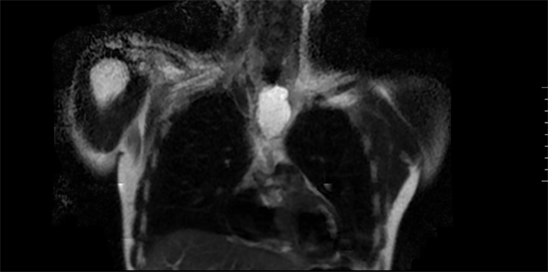

In order to assess the intrathoracic extension, and to avoid further irradiation to the patient, amagnetic resonance imaging (MRI) (Figure 3 and Figure 4) is requested in which a cystic lesion (78 × 37 × 26 mm) is observed, located in the cervicothoracic transition with anterosuperior mediastinal extension, possibly related to the thyroid without nodular enhancements. No septal contrast enhancement is seen after the administration of gadolinium to rule out cystic neoplasia.

Figure 3. Thoracic MRI. The cystic mass is observed in anterior mediastinum.

Figure 4. Thoracic MRI. Sagittal view.